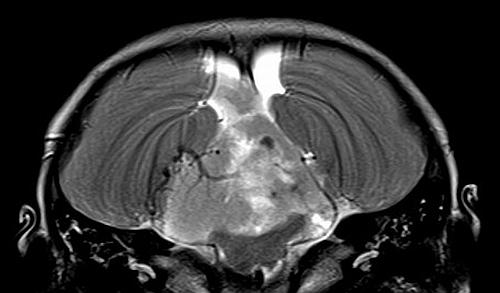

Tumora era dezvoltata in trunchiul cerebral si extinsa in canalul medular, Foto: MedLife

La inceputul acestei luni, in cadrul Life Memorial Hospital din Bucuresti, medicii au reusit sa indeparteze complet o tumoare cu diametrul de 7 cm, la un copil de 2 ani si cinci luni. Indepartarea in totalitate a tumorii de ventricul 4 a durat 16 ore, din care 15, petrecute la microscop. Intens vascularizata, tumoarea voluminoasa dezvoltata din trunchiul cerebral in ventricolul 4 si extinsa in canalul medular a fost abordata pe cai naturale, fara a rani sau retracta cerebelul, a declarat pentru MedLive.ro dr. Sergiu Stoica, medic specialist neurochirurg. La zece minute dupa operatie, copilul s-a trezit si a strigat-o pe “mama”. La o saptamana dupa operatie, a fost externat.

Tumora trebuie abordata pe cai naturale, fara a rani sau retracta tesutul nervos din jur. In cazul copilului de 2 ani si 5 luni s-a folosit un abord velotonsilar pentru a ajunge in ventricolul 4 fara a taia sau retracta cerebelul. Riscurile sunt nenumarate: deces intraoperator, stare vegetativa, deficite neurologice etc.), insa sunt foarte mici, sub 1%, in mainile unor chirurgi antrenati.